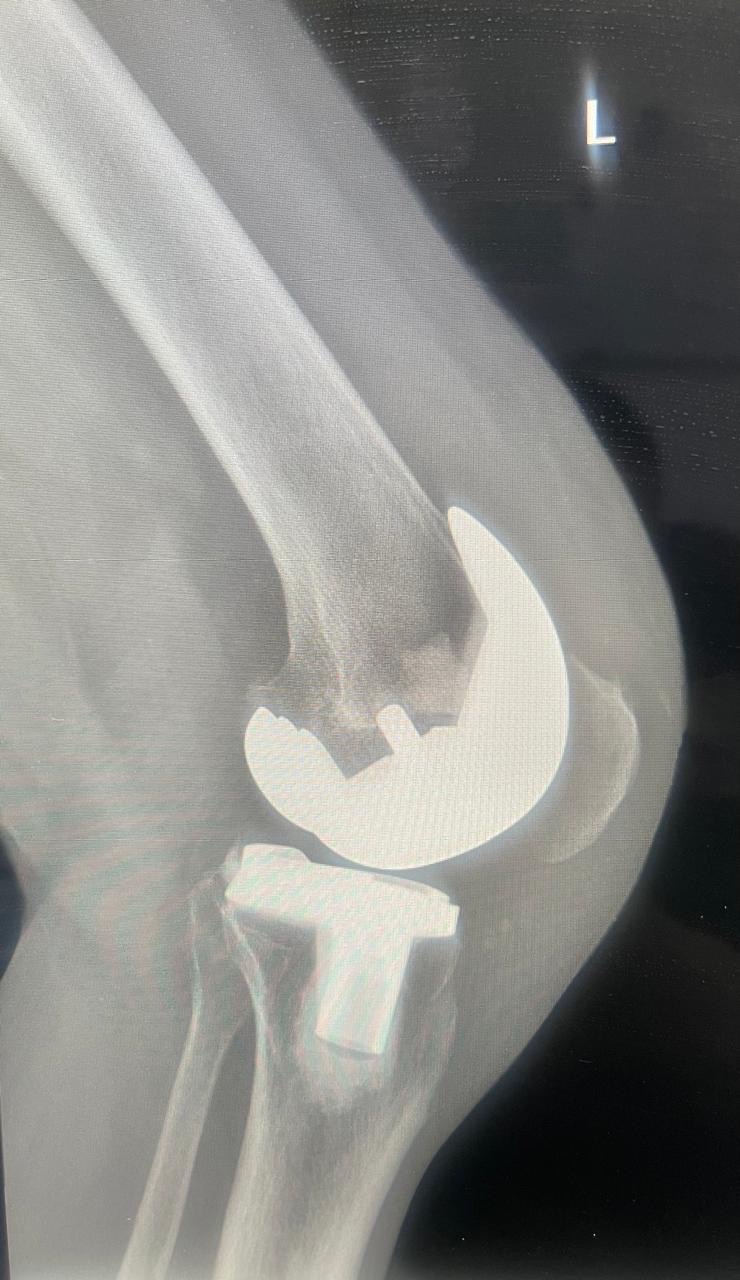

أعلن مستشفى القطيف المركزي إطلاق وحدة تخصصية لتبديل وترميم المفاصل، متوجاً انطلاقتها بإجراء 30 عملية جراحية ناجحة للركبة، لتعزيز كفاءة الرعاية الطبية وتطوير الخدمات وفق أحدث المعايير العالمية المعتمدة.

وأوضح المستشفى التابع لتجمع الشرقية الصحي، أن الوحدة الجديدة انضمت رسمياً للوحدات التخصصية بقسم العظام، مبيناً أن نجاح العمليات الثلاثين يعكس جاهزية الكوادر الطبية وتوفر التقنيات المتقدمة.

وبيّنت الجهات الطبية أن الوحدة تقدم منظومة رعاية متكاملة، تبدأ بتقييم وتشخيص دقيق لحالات تآكل المفاصل والإصابات المزمنة، وصولاً للتدخلات الجراحية المبتكرة.

وأضافت أن خطة العلاج تكتمل بتقديم برامج تأهيل وعلاج طبيعي متخصصة، تستهدف تسريع وتيرة تعافي المرضى بشكل آمن، وتحسين جودة حياتهم اليومية.